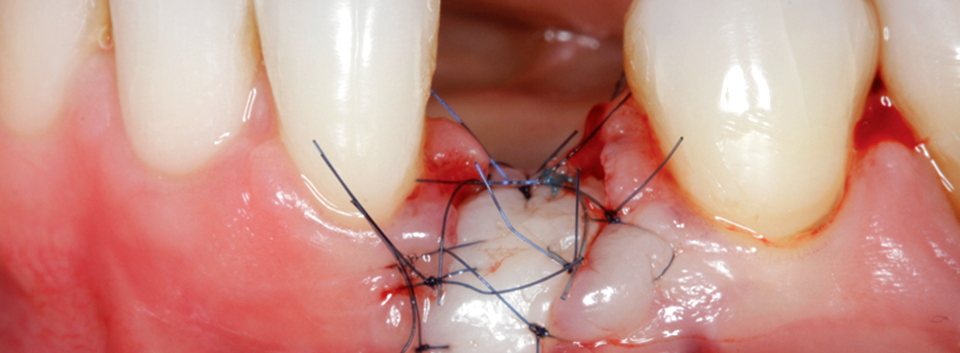

1) Immediate Implant placement with Socket & Soft Tissue Grafts

The patient treatment by faculty will focus on advanced surgical treatment with implant placement and GBR/soft tissue grafting in the Anterior esthetic zone.